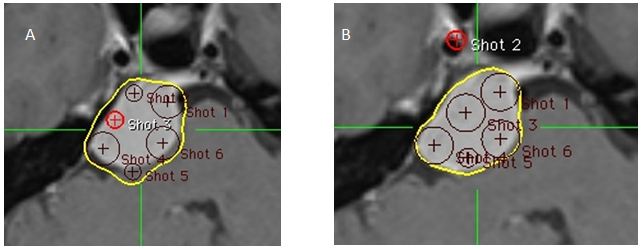

Hình 21: Hình ảnh đặt kế hoạch điều trị cho 2 tổn thương trong một ma trận

Ma trận tính toán được thể hiện (ma trận màu đỏ được chọn). Các shot có thể chỉ được đặt trong ma trận.

Bệnh nhân Ngô Hữu V.; nam, 60 tuổi. Chẩn đoán: Ung thư phổi di căn tiểu não. Chỉ định xạ phẫu: dao gamma quay (RGK) liều 22Gy”

Kỹ thuật 46: Trọng số kỹ thuật

Hình 22: Hình ảnh lập kế hoạch cho 2 khối u: Hình (A)Khối u 2 được bao phủ tốt nhưng khối u 1 không nằm trong đường đồng liều điều trị. Hình (B,C) thêm một shot để bao phủ khối u 1 để tạo ra hiệu quả cần thiết:

Bệnh nhân Ngô Hữu V.; nam, 60 tuổi. Chẩn đoán: Ung thư phổi di căn tiểu não, chỉ định: xạ phẫu dao gamma quay (RGK) liều 22Gy”